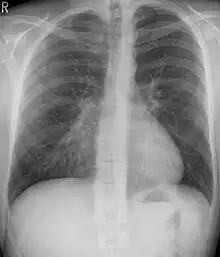

Pectus excavatum on PA chest radiograph with shift of heart shadow to the left and radioopacity of the right paracardiac lung field

Chest x-rays are also useful in the diagnosis. The chest x-ray in pectus excavatum can show an opacity in the right lung area that can be mistaken for an infiltrate (such as that seen with pneumonia).[20] Some studies also suggest that the Haller index can be calculated based on chest x-ray as opposed to CT scanning in individuals who have no limitation in their function.[21]